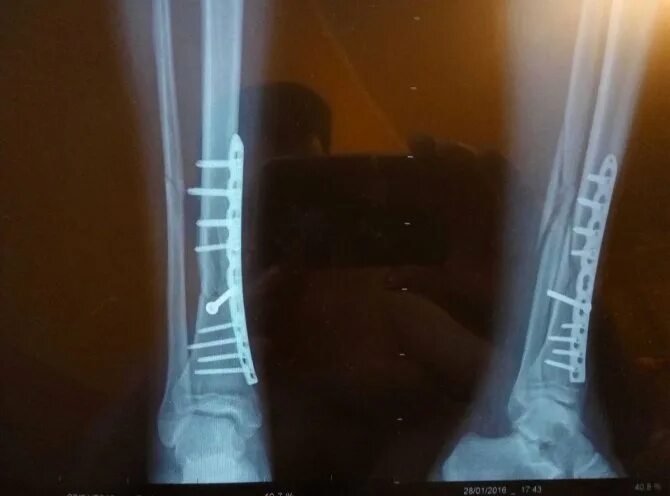

Сколько срастается малая берцовая кость